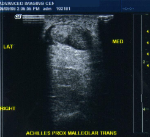

Achilles Tendon: Partial Thickness tear at the anterior surface; split longitudinal tear